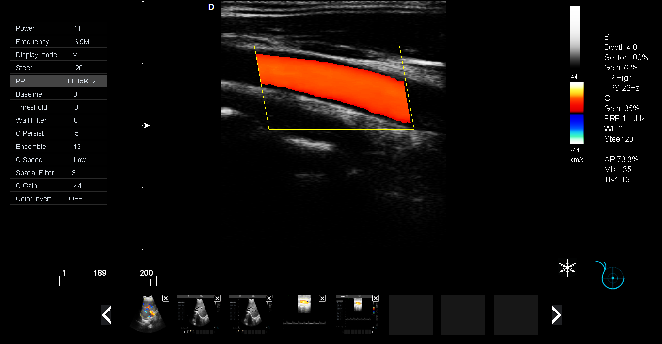

頸動(dòng)脈血流:

頸動(dòng)脈彩超是診斷、評(píng)估頸動(dòng)脈壁病變的有效手段之一,在動(dòng)脈粥樣硬化的流行病學(xué)調(diào)查和對(duì)動(dòng)脈粥樣硬化預(yù)防、治療試驗(yàn)的有效性評(píng)價(jià)中起著關(guān)鍵作用。

頸動(dòng)脈彩超不僅能清晰顯示血管內(nèi)中膜是否增厚、有無(wú)斑塊形成、斑塊形成的部位、大小、是否有血管狹窄及狹窄程度、有無(wú)閉塞等詳細(xì)情況, 并能進(jìn)行準(zhǔn)確的測(cè)量及定位,還能對(duì)檢測(cè)動(dòng)脈的血流動(dòng)力學(xué)結(jié)果進(jìn)行分析。